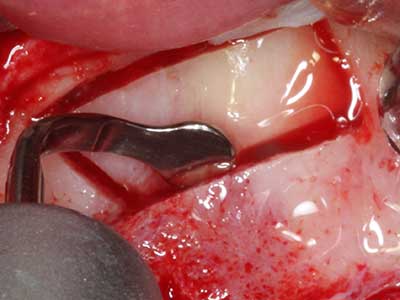

Piezosurgery has additional advantages when harvesting bone blocks. In addition to the high precision with osteotomy described above, the use of the thin saw tips specifically minimizes loss of material. Greater loss of material during harvesting can be expected with the thicker instrument tips, particularly when using Lindemann drills (Lakshmiganthan, Gokulanathan et al. 2012). The basal separation, which is necessary particularly for retromolar block transplants, is simplified by specially designed rectangular saws, with the result that piezosurgery is viewed as a precise, simple and safe procedure for harvesting retromolar bone blocks (Happe 2007) (Fig. 1-12).